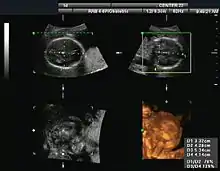

Obstetrical sonography was originally developed in the late 1950s and 1960s by Sir Ian Donald[16][17] and is commonly used during pregnancy to check the development and presentation of the fetus. It can be used to identify many conditions that could be potentially harmful to the mother and/or baby possibly remaining undiagnosed or with delayed diagnosis in the absence of sonography. It is currently believed that the risk of delayed diagnosis is greater than the small risk, if any, associated with undergoing an ultrasound scan. However, its use for non-medical purposes such as fetal "keepsake" videos and photos is discouraged.[18]

Obstetric ultrasound is primarily used to:

- Date the pregnancy (gestational age)

- Confirm fetal viability

- Determine location of fetus, intrauterine vs ectopic

- Check the location of the placenta in relation to the cervix

- Check for the number of fetuses (multiple pregnancy)

- Check for major physical abnormalities.

- Assess fetal growth (for evidence of intrauterine growth restriction (IUGR))

- Check for fetal movement and heartbeat.

- Determine the sex of the baby